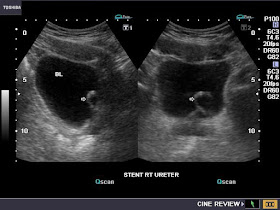

This patient underwent surgery for the removal of a staghorn calculus from the right kidney. A right ureteric stent was inserted to facilitate the smooth passage of urine in the right ureter. Ultrasound image shows the upper end of the DJ or Double J stent (JJ stent) in the right renal pelvis.

The lower end of the JJ right ureteric stent is seen in the urinary bladder as a coiled echogenic linear (tubular echo). The presence of coils/ pigtail loops at both ends pf the ureteral stent prevents its displacement or migration. Ultrasound imaging also helps to rule out other complications of ureteral stent like infection, migration, obstruction and malpositioning.

The sonographic image above ( case-2) shows the lower end of stent in urinary bladder

Just added this image (case-2) showing the DJ stent tip (upper end) clearly in side the renal pelvis of the right kidney (view made possible due to minimal fluid/ urine in the renal pelvis)- see image just above.